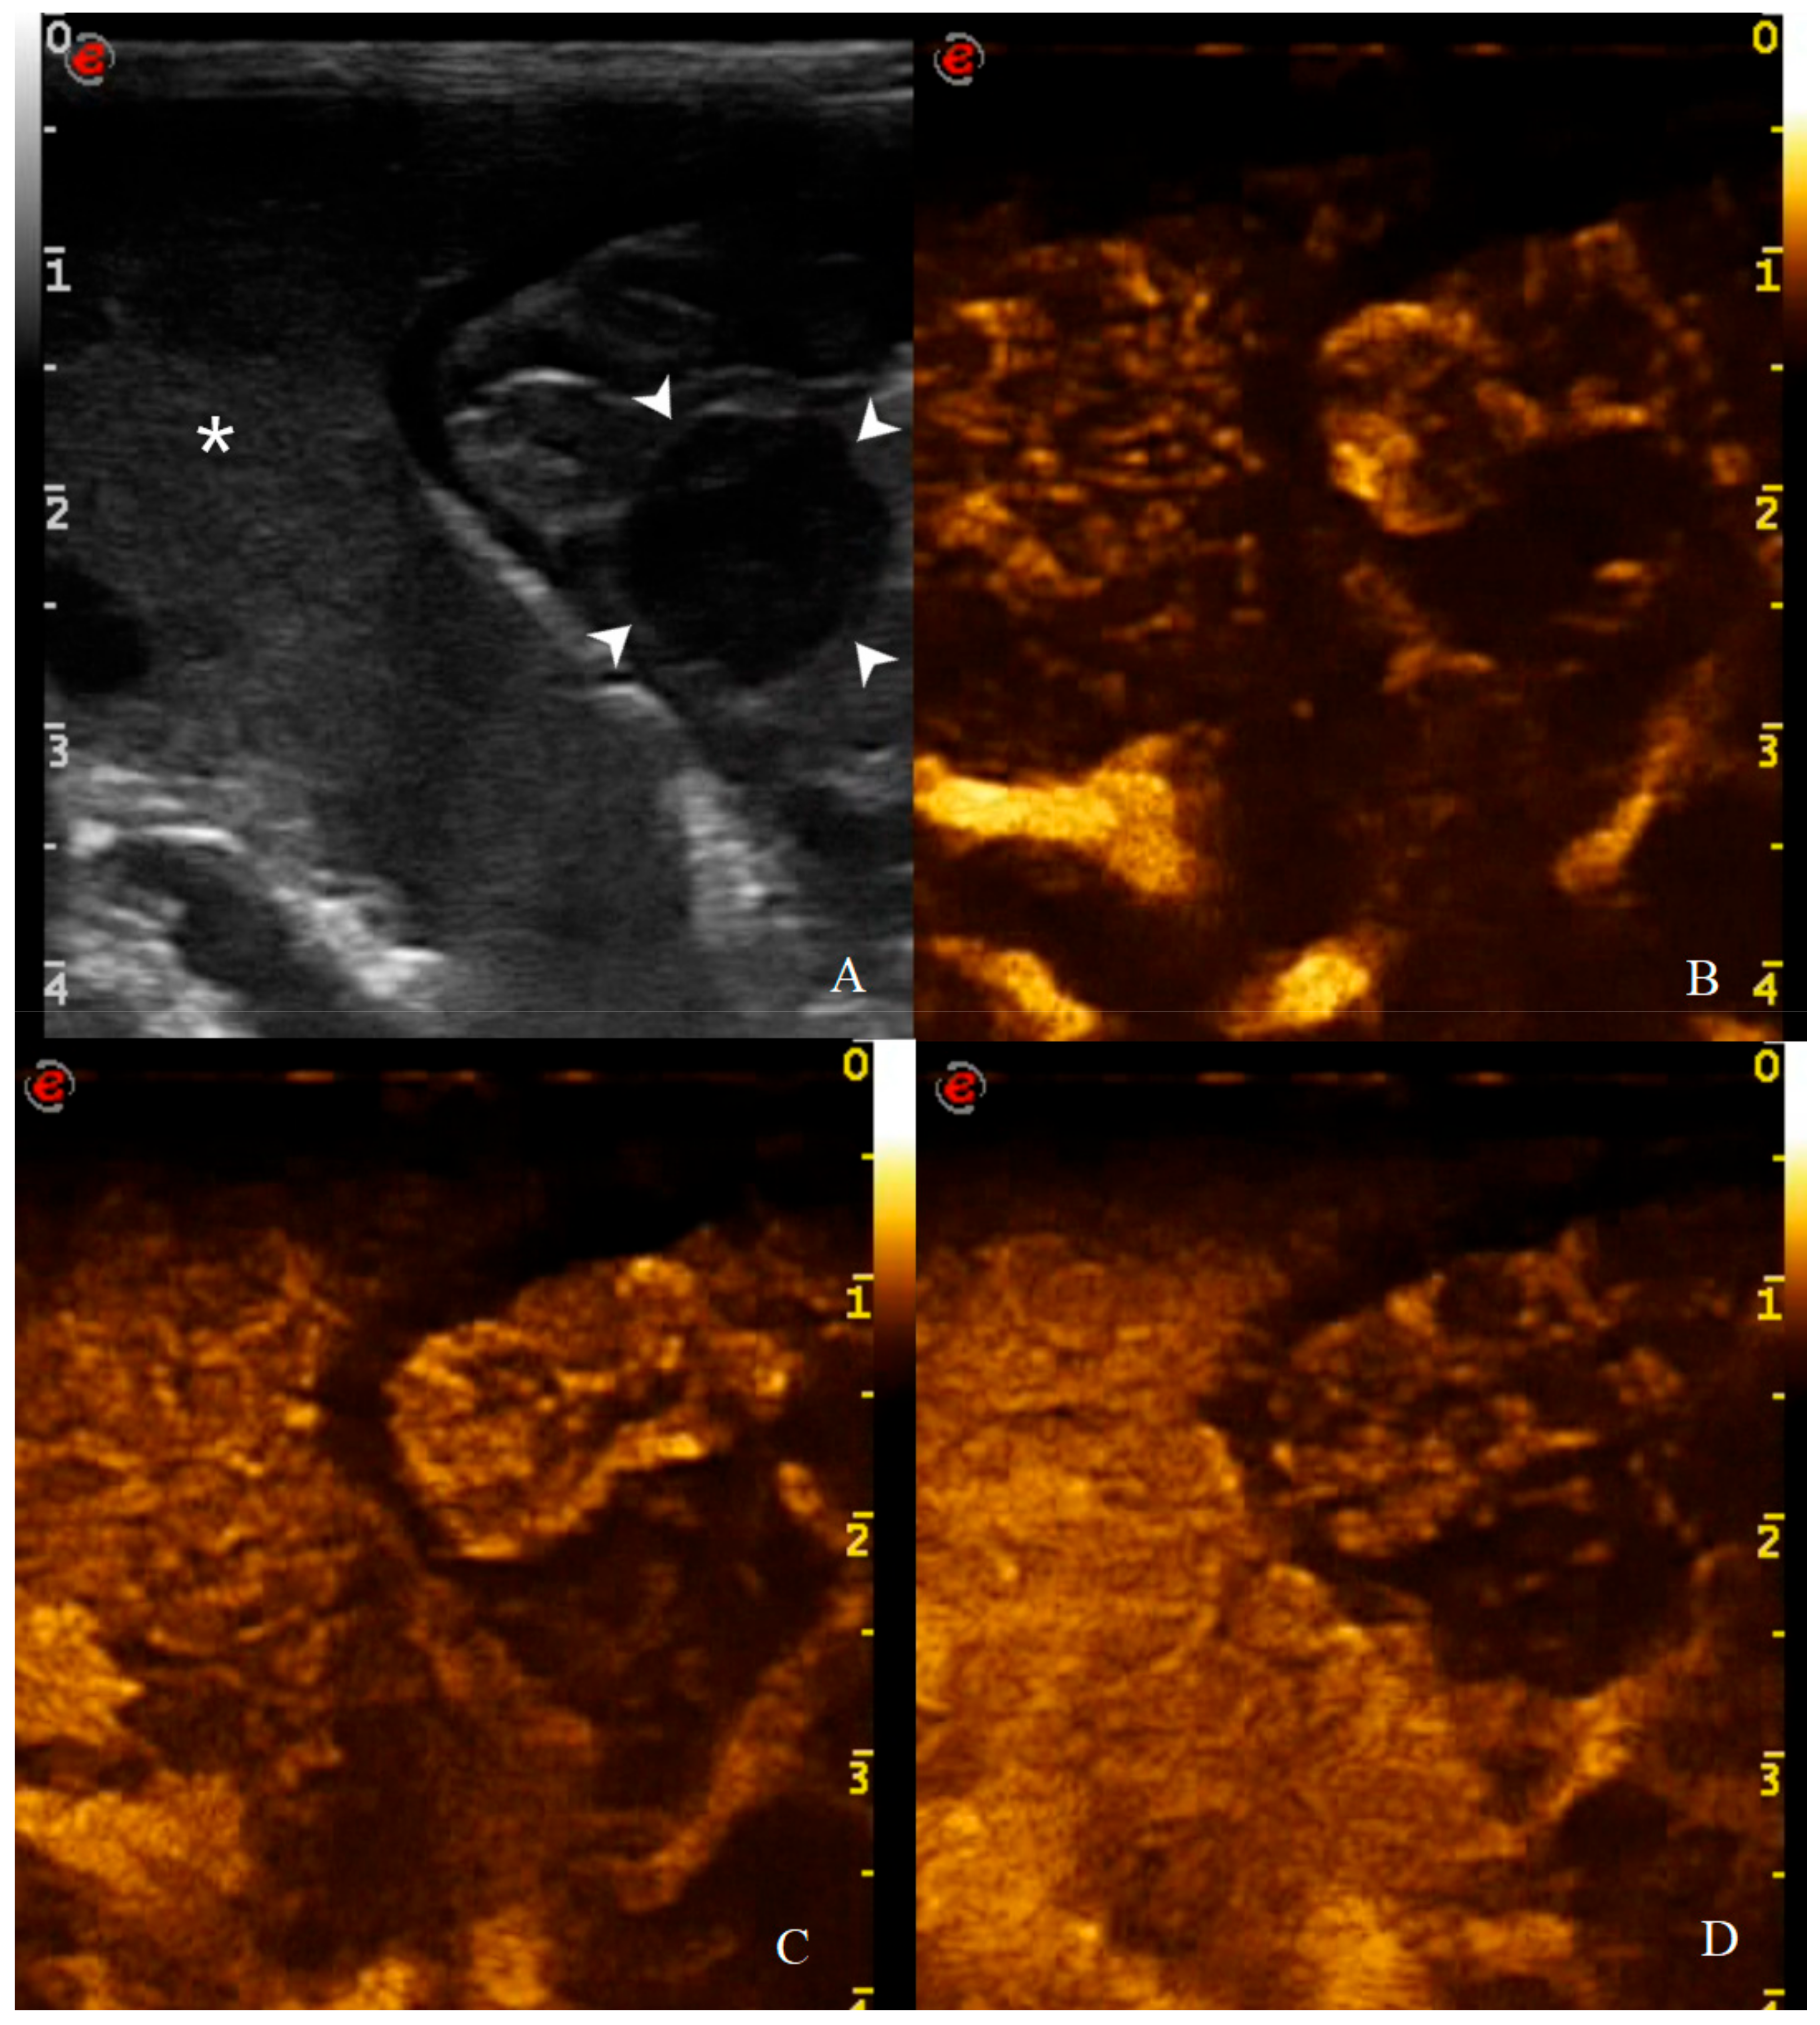

3.2. Analysis of B-Mode Examination

3.3. Analysis of CEUS Examination